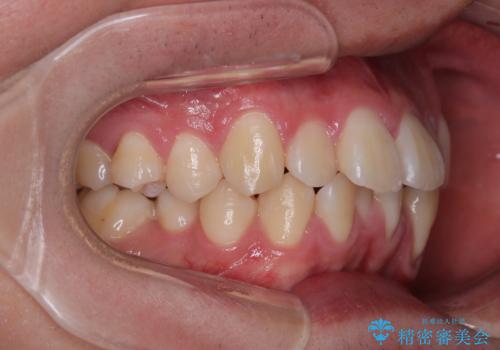

- 全顎的なデコボコを気にして来院された患者様です。

特に前歯のデコボコが顕著であり、上下左右第一小臼歯の4本を抜歯し、ワイヤー装置を使用して咬み合わせ高さを改善しながら、歯列を整えて行くこととしました。

移動が順調に進み、1年半の短期間で治療を終えることができました。

前方に突出した上顎前歯の傾斜も改善されました。